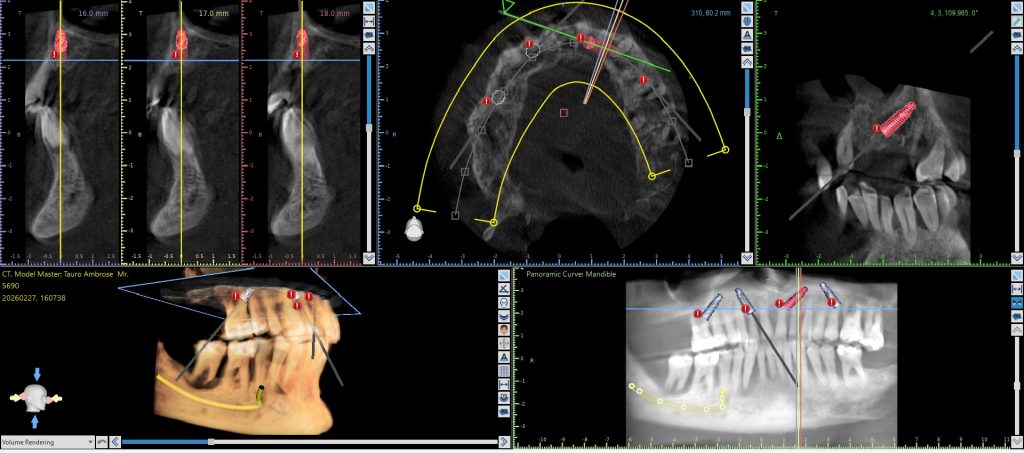

3. Digital Treatment Planning Software:

Before any surgery, we design your entire procedure digitally. Your CBCT and scan data are combined into a 3D plan showing the precise angle, position, and depth of every implant. Every decision is made in advance — not during surgery. This plan also drives your custom surgical guide.